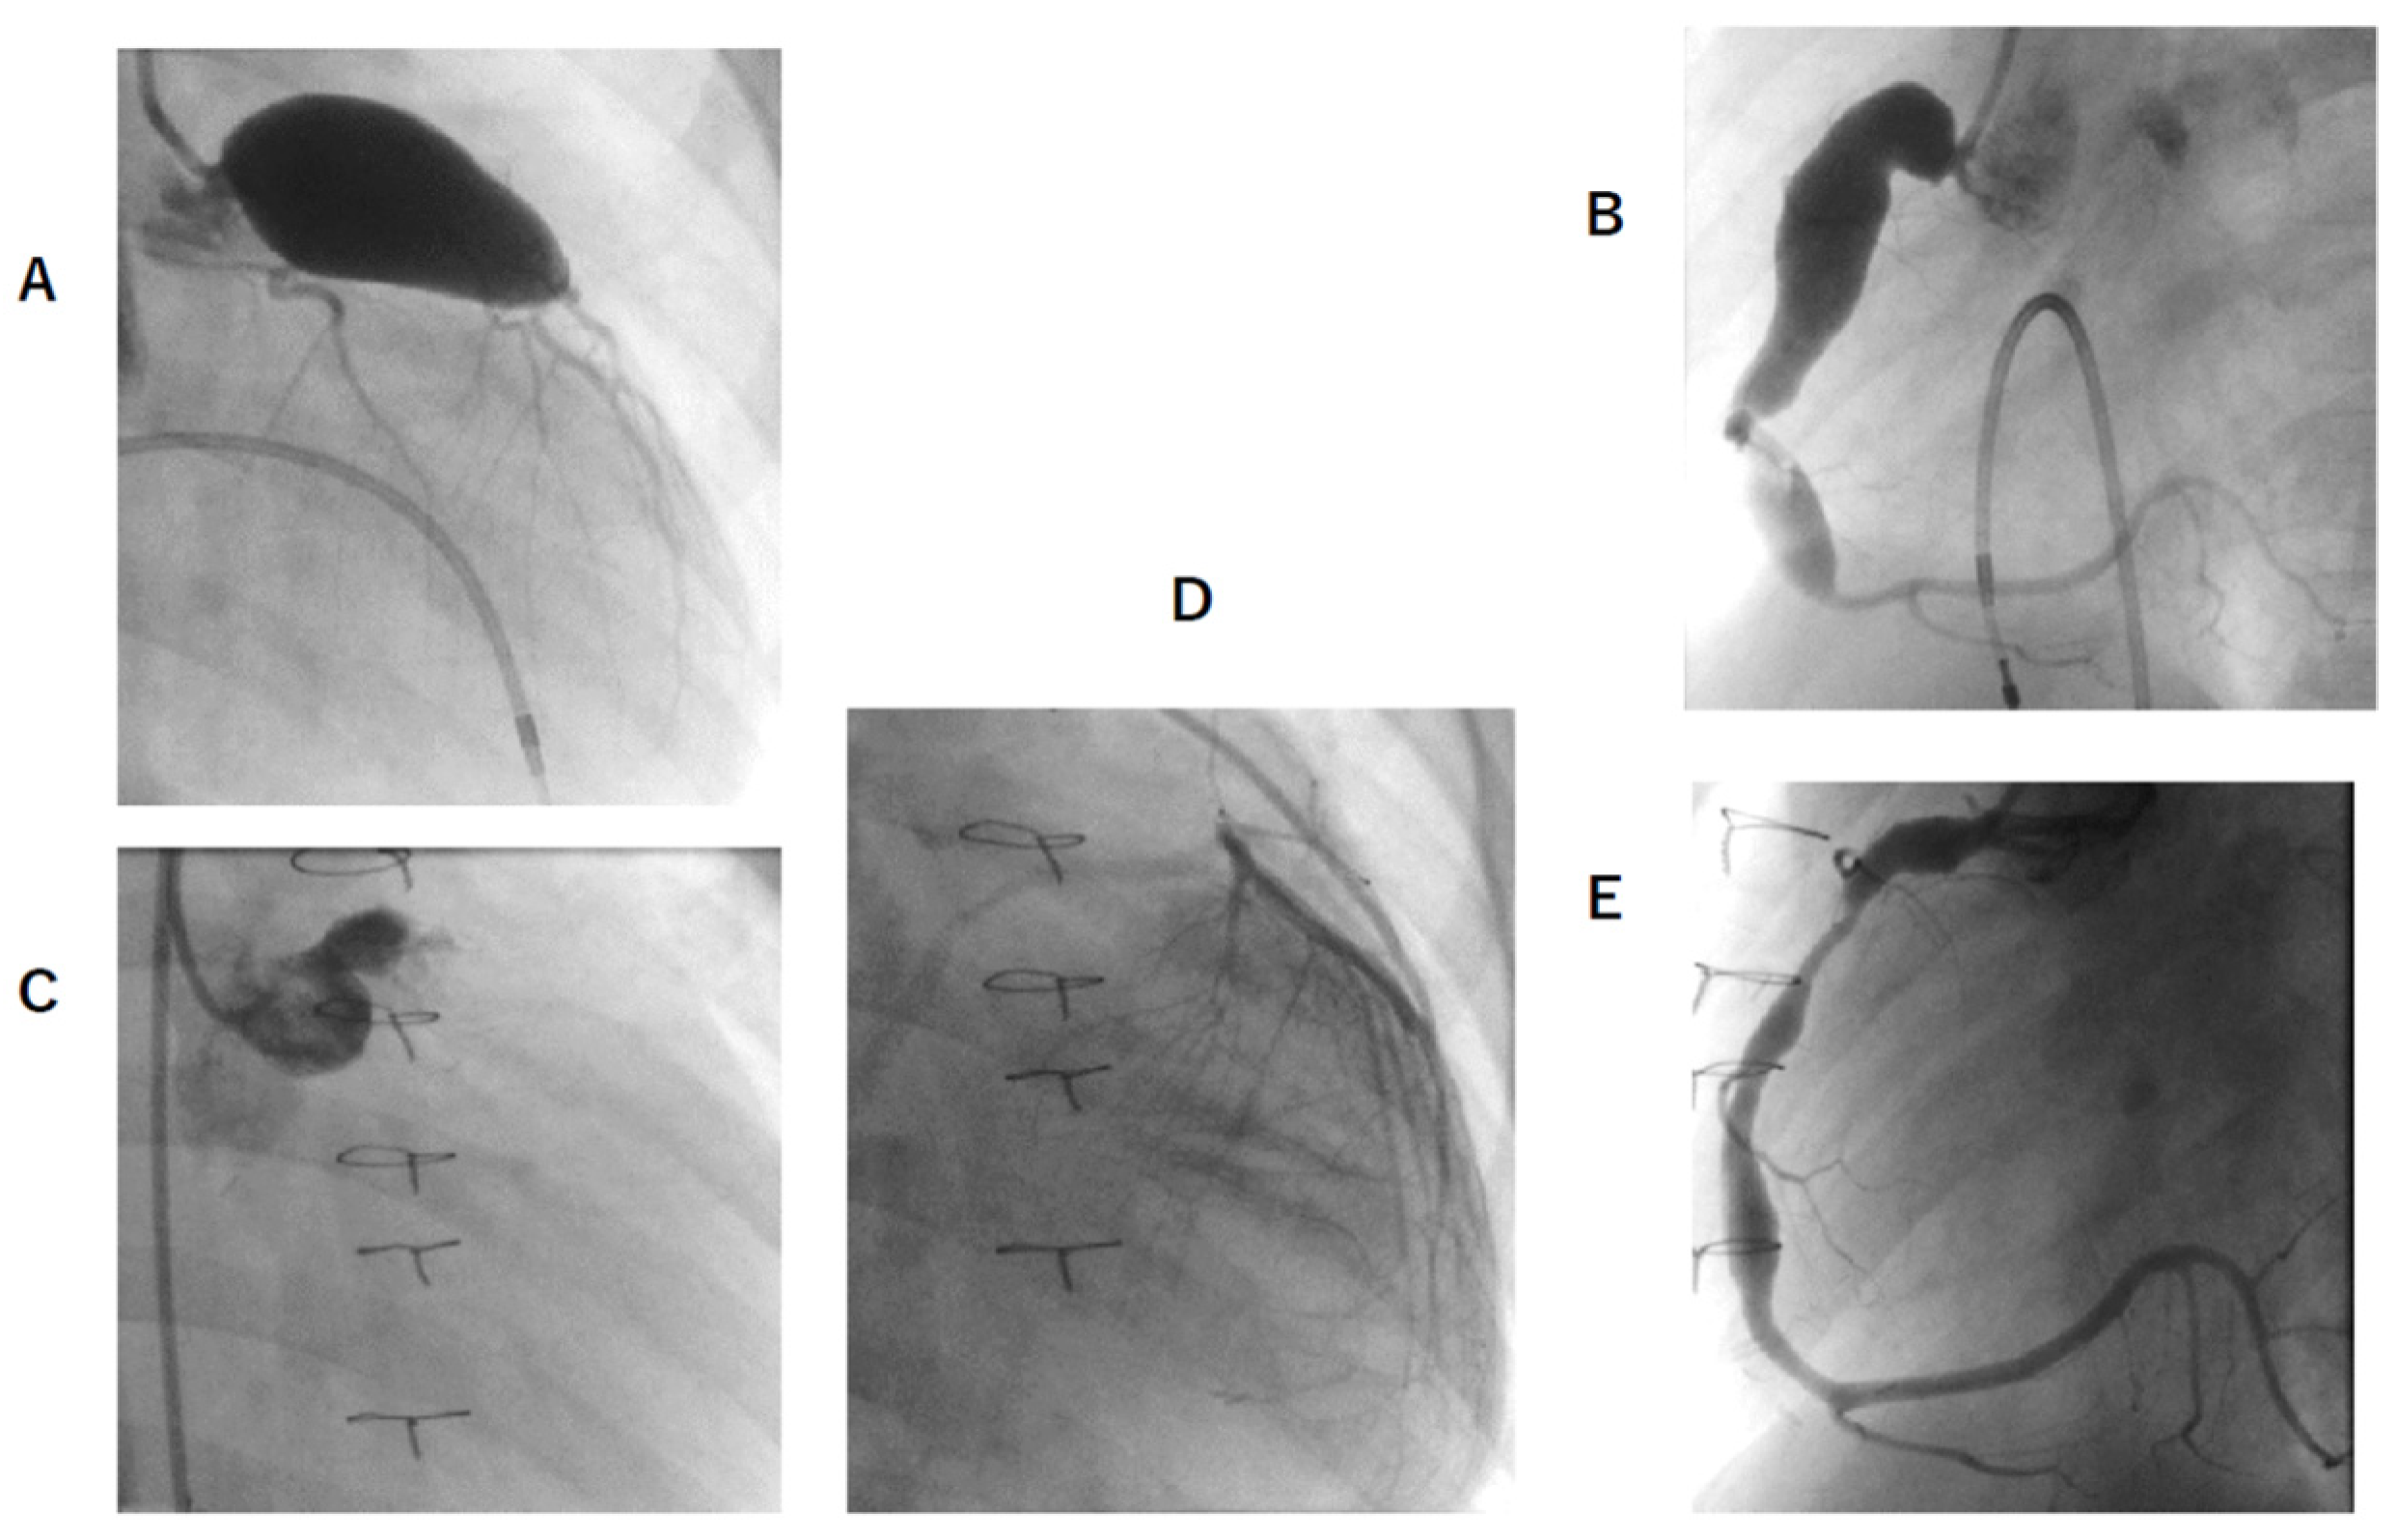

3.4. Latest CAG Findings